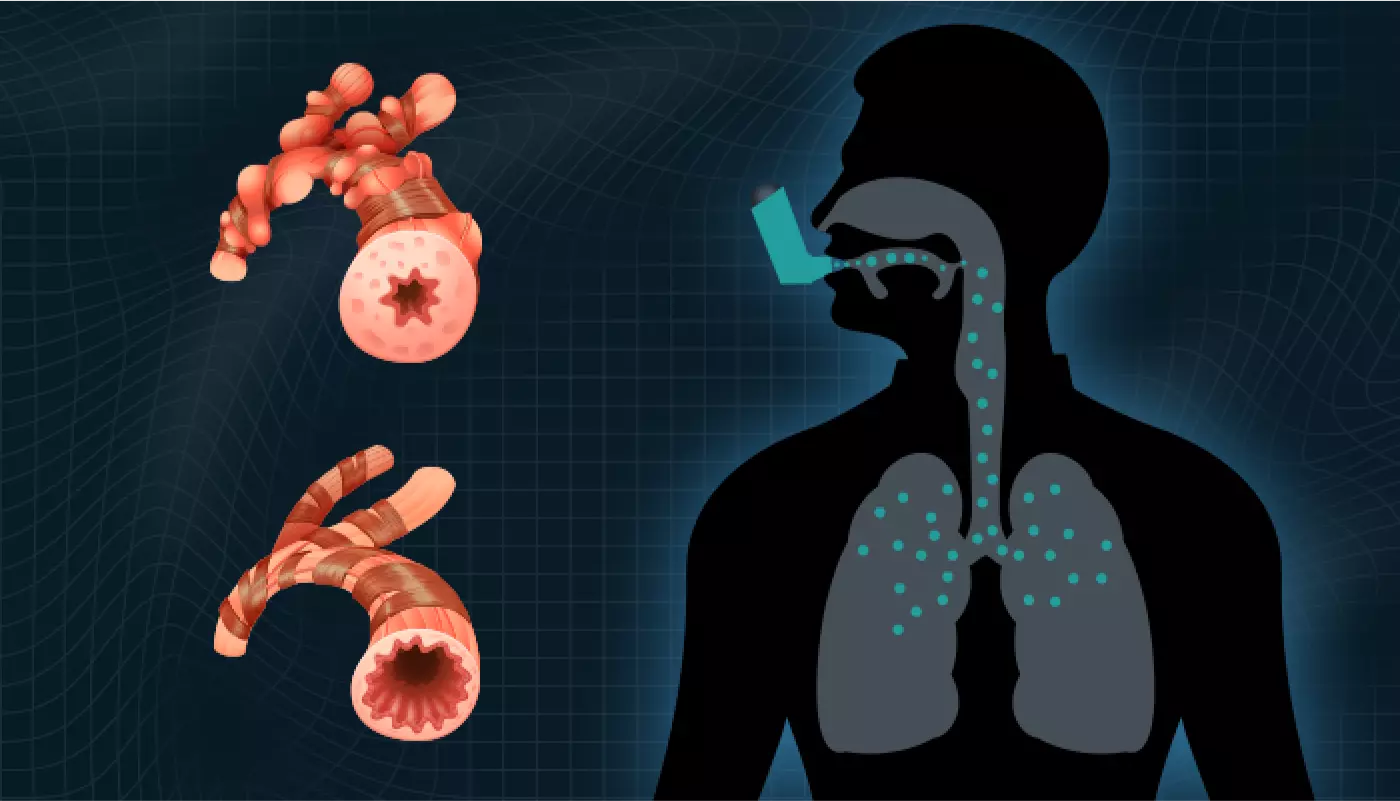

OPEP stands for “Oscillating Positive Expiratory Pressure.” To cut a long story short, it means putting positive pressure on your lungs to open up your airways, which makes breathing easier.

As a bonus, the vibrations caused by OPEP dislodge the thick mucus caused by certain respiratory conditions. After OPEP, you can expel the mucus by coughing, reducing the tight grip it exerts on your airways.

That means using RespiraFix is – literally – a breath of fresh air delivered directly into your lungs!

Even better, as your airways open up, you’ll be able to take deeper, more satisfying breaths. This not only delivers more precious oxygen to your bloodstream but also increases your lung capacity over time. It’s a “virtuous circle” that will help you feel healthier and breathe better.